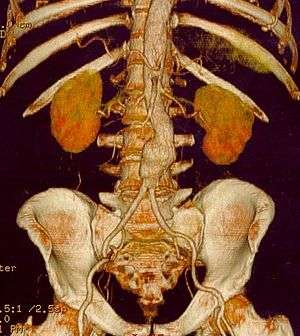

CT reconstruction image of an abdominal aortic aneurysm | |

Abdominal aortic aneurysm

Abdominal aortic aneurysms (AAAs) are more common than their thoracic counterpart. One reason for this is that elastin, the principal load-bearing protein present in the wall of the aorta, is reduced in the abdominal aorta as compared to the thoracic aorta. Another is that the abdominal aorta does not possess vasa vasorum, the nutrient-supplying blood vessels within the wall of the aorta. Most AAA are true aneurysms that involve all three layers (tunica intima, tunica media and tunica adventitia). The prevalence of AAAs increases with age, with an average age of 65–70 at the time of diagnosis. AAAs have been attributed to atherosclerosis, though other factors are involved in their formation.

The risk of rupture of an AAA is related to its diameter; once the aneurysm reaches about 5 cm, the yearly risk of rupture may exceed the risks of surgical repair for an average-risk patient. Rupture risk is also related to shape; so-called "fusiform" (long) aneurysms are considered less rupture prone than "saccular" (shorter, bulbous) aneurysms, the latter having more wall tension in a particular location in the aneurysm wall.